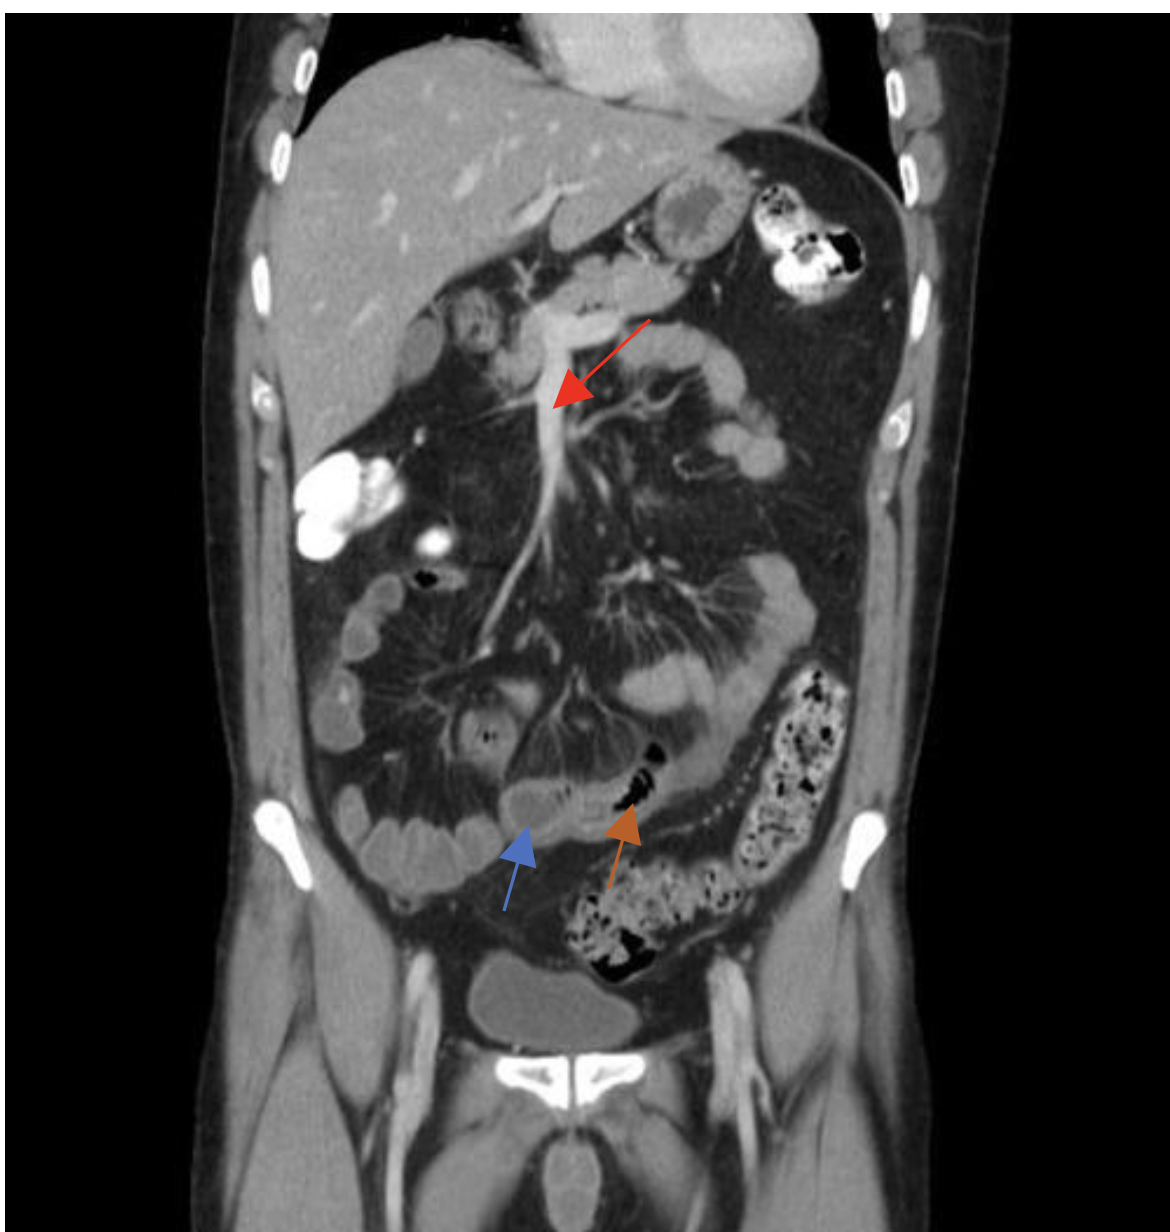

של חולה קרוהן MRI בתמונה

מה החצים מסמלים?

גדושים SMA חץ אדום- הענפים של ה

חץ כחול- דופן המעי עבה ומלאה מים

חץ כתום- כיבים

בנוסף ניתן לראות קשריות לימפה נפוחות שמעידות על דלקת (?)